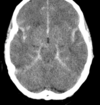

Describe how you manage NPH [2+]